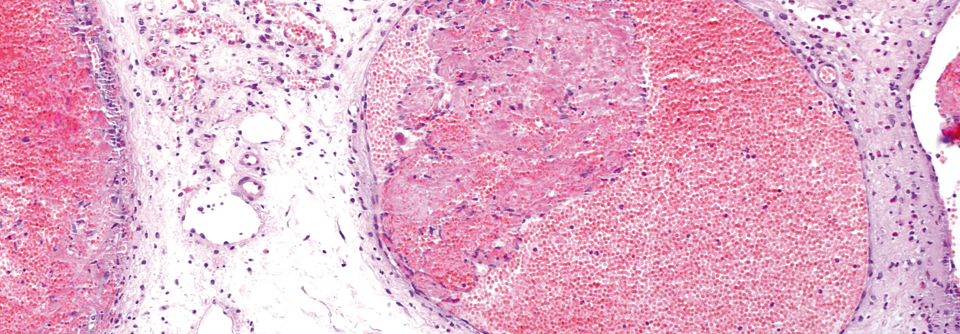

Infantile Hämangiome Erdbeerflecken nicht immer harmlos

Die meisten infantilen Hämangiome erfordern keine Behandlung. Ungefähr jeder zehnte junge Patient mit Blutschwämmchen sollte jedoch besser bei einem Spezialisten vorstellig werden – mancher davon sogar schnellstmöglich. Ein Score hilft dabei, kritische Fälle zu erkennen.